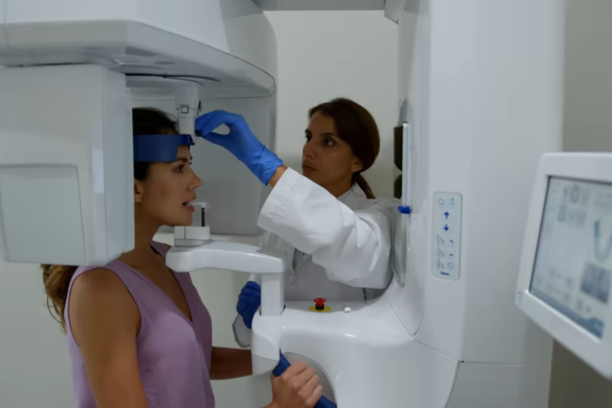

تقع أفضل عيادة أسنان في جدة داخل مجمع درياق الطبي، حيث تقدّم العيادة رعاية شاملة وتشخيصًا دقيقًا لمشاكل الفم والأسنان باستخدام أحدث التقنيات، بإشراف نخبة من أطباء الأسنان المتخصصين، وفي بيئة مريحة وآمنة مناسبة لجميع أفراد العائلة.

تُعد عيادة أسنان مجمع درياق الطبي بجدة الخيار الأمثل للأشخاص الباحثين عن رعاية طبية متميزة لأسنانهم، بفضل فريقها الطبي المتخصص وتقنياتها الحديثة في التشخيص والعلاج. تمتاز العيادة بموقعيها الحيويين في حي الحمدانية وحي الفلاح، وتوفر بيئة طبية مريحة وآمنة للمرضى من مختلف الأعمار، مع عناية دقيقة بحالات علاج العصب، اللثة، التجميل، والتقويم، مما يجعلها وجهة موثوقة لكل من يهتم بصحة فمه وابتسامته.

تقدّم عيادة الأسنان في جدة – مجمع درياق الطبي مجموعة متكاملة من الخدمات التشخيصية والعلاجية التي تغطي جميع احتياجات صحة الفم والأسنان. تشمل الخدمات:

إذا كنت تبحث عن دكتور أسنان يقدم رعاية طبية متميزة ويهتم بأدق تفاصيل صحة الفم والابتسامة، فإن مجمع درياق الطبي في جدة يعد من الخيارات الموثوقة التي يقصدها العديد من المراجعين. يضم المجمع نخبة من أطباء الأسنان ذوي الخبرة الواسعة في تشخيص وعلاج مختلف مشكلات الأسنان، ويعمل تحت إشراف فريق متخصص يجمع بين الخبرة العملية والمهارة التجميلية والدقة العلاجية. كما يعتمد الفريق على أحدث التقنيات في علاج اللثة، والعصب، وتركيبات الأسنان، والتقويم، ضمن بيئة طبية مريحة وآمنة تراعي راحة المراجع وتمنحه شعورًا بالثقة والاطمئنان في كل خطوة من خطوات العلاج.

تحظى عيادة الأسنان في جدة داخل مجمع درياق الطبي بثقة مئات المراجعين بفضل التزامها بتقديم رعاية طبية دقيقة تراعي احتياجات المريض والأسرة معًا. يجمع القسم بين الخبرة الطبية المتخصصة والتقنيات الحديثة في التشخيص والعلاج، مما يضمن نتائج دقيقة وسرعة في الاستجابة. كما يحرص الفريق الطبي على خلق بيئة مريحة وآمنة للمرضى، مع أسلوب تعامل إنساني يخفف من رهبة الزيارة ويمنح المراجع شعورًا بالطمأنينة والثقة الكاملة في جودة الرعاية المقدّمة.